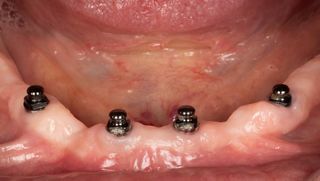

7c. The patient was seen again 15 days after surgery. The prosthesis was then removed for the first time since the surgery. The soft tissues were healthy with little inflammation. The implants were stable.

The postoperative period was uneventful, with little pain and a slight haematoma.

The prosthesis was cleaned and replaced. The patient was advised to remove two to three times a week for the first three months of osseointegration.

7c

8a. 8b. Follow-up at one year. The implants are osseointegrated. There is some tartar build-up on the Optiloc connector, which will require careful maintenance to avoid damaging the ADLC surface.

The patient is delighted with the result and the prosthesis is still just as secure with the original retention inserts.

8a

8b